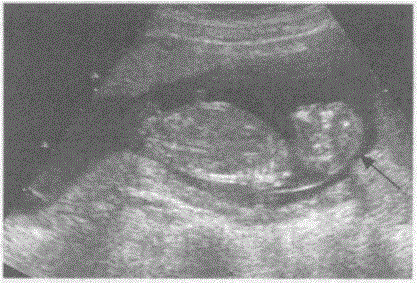

问题 临床资料:女,29岁,孕18周。 超声综合描述:缺少颅骨光环,胎头可见"瘤结"状块状物。 超声提示:

选项 A.无脑儿 B.脑积水 C.脑膜膨出 D.露脑畸形

答案 A